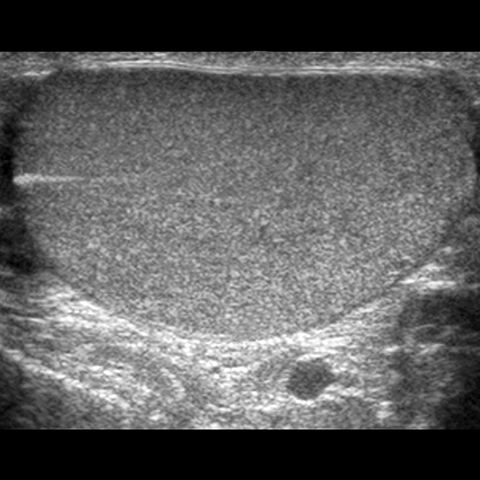

Ovoid shape of testis, ultrasound [4 of 4]